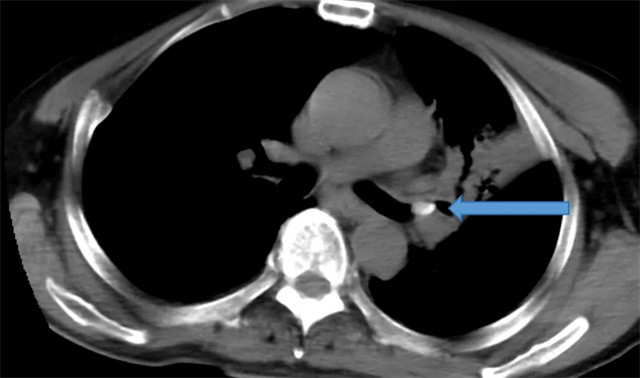

术前CT检查影像

眼见老人身体状况日益不佳,家人急忙带着郑大爷前往信丰县中医院就诊。入院后,呼吸内科医师详细询问病史并进行体格检查,考虑到患者有长期进食呛咳史且咳嗽咳痰症状持续不愈,立即安排胸部 CT 检查。检查结果显示,郑大爷左肺上叶支气管存在异物,且已合并左肺上叶尖后段肺不张,这正是导致他反复咳嗽、咳痰的根本原因。